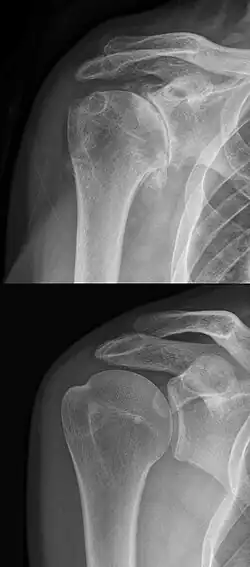

Im Röntgenbild zeigt sich eine Verformung des Oberarmkopfes im Sinne von spornartigen Ausziehungen (Osteophyten). Durch die Minderung der Dicke des Gelenkknorpels verschmälert sich der sichtbare Gelenkspalt. Nach oben, zum Akromion hin, findet sich häufig ebenfalls eine Verschmälerung als Zeichen des Verschleißes der Rotatorenmanschette.[2] Dies ist aber eine eigene krankhafte Veränderung, die auch ohne Omarthrose auftreten kann.